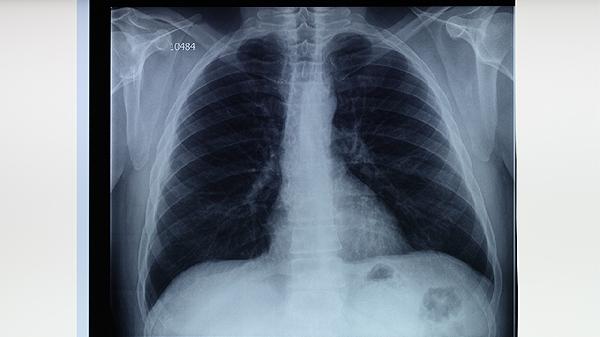

胸部X線檢查可發(fā)現(xiàn)肺結(jié)核的典型表現(xiàn)如上葉尖后段或下葉背段浸潤(rùn)性病變、空洞形成等。胸部CT檢查能更清晰顯示病變細(xì)節(jié),對(duì)早期病變、不典型病變和小病灶的檢出率更高。影像學(xué)表現(xiàn)需結(jié)合臨床表現(xiàn)和其他檢查結(jié)果綜合判斷。